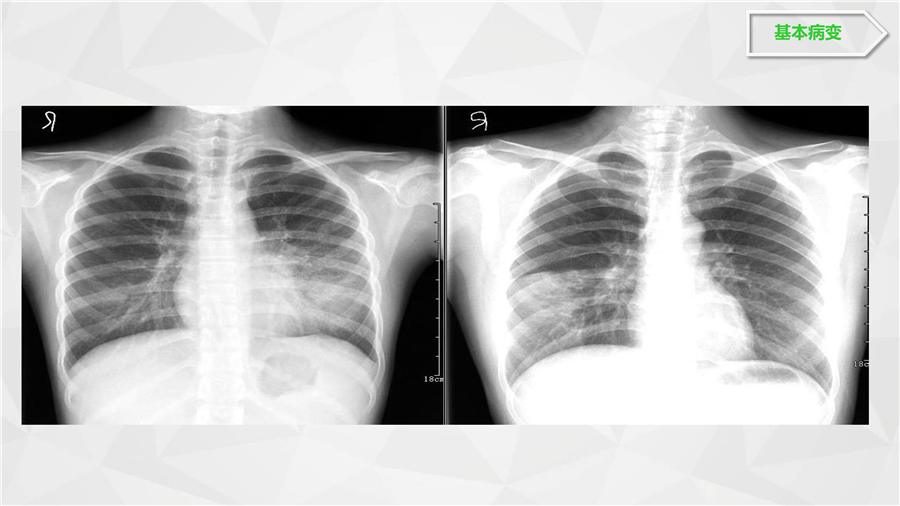

呼吸系统二